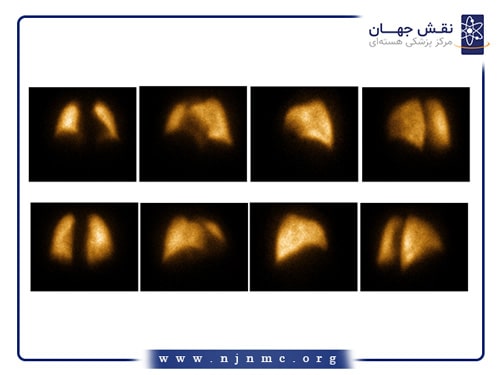

اسکن هسته ای قلب

اسکن هستهای قلب یک روش تصویربرداری تشخیصی میباشد که جریان خون به عضله قلب را ارزیابی میکند. این روش به تشخیص بیماری عروق کرونر (CAD) و ارزیابی ميزان بافت زنده عضله قلب پس از وقوع انفاركتوس کمک میکند. این آزمایش شامل تزریق یک ردیاب رادیواکتیو است که سپس توسط دستگاه مخصوص تصویربرداری میشود تا نشان دهد که خونرسانی به عضله قلب، در حالت استراحت و در هنگام استرس (ورزش یا ناشی از دارو)، به چه صورت میباشد.